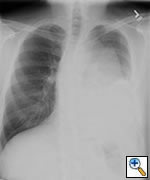

Any anterior mediastinal mass (Figures 1, 2) must be considered suspect for germ cell tumor, especially in a young male. Errors in diagnosis are not uncommon and can result in mismanagement of a potentially curable patient. All patients with an anterior mediastinal mass should have alpha-fetoprotein (AFP), β-human chorionic gonadotropin (β-HCG), and lactate dehydrogenase (LDH) levels drawn at the outset. The different types of germ cell histologies are shown in Figure 3.